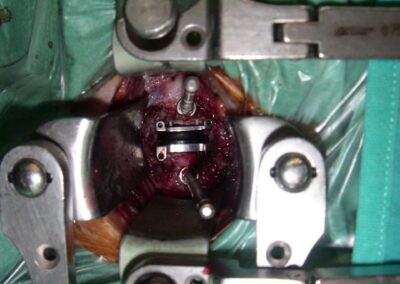

Cuando se trata de aliviar la presión sobre un nervio y el dolor de cuello, la cirugía usualmente incluye una extracción completa del disco o discectomía, seguido por el implante de un dispositivo espaciador o una prótesis total de disco. Esta cirugía se hace en la parte anterior del cuello (se le llama microdiscectomía y artrodesis o prótesis discal anterior). Afortunadamente, estos procedimientos muchas veces pueden realizarse usando técnicas de invasión mínima. La cirugía de invasión mínima no requiere incisiones grandes, sino que hace pequeños cortes y usa instrumentos y dispositivos minúsculos especializados durante la operación, como un microscopio y un endoscopio.